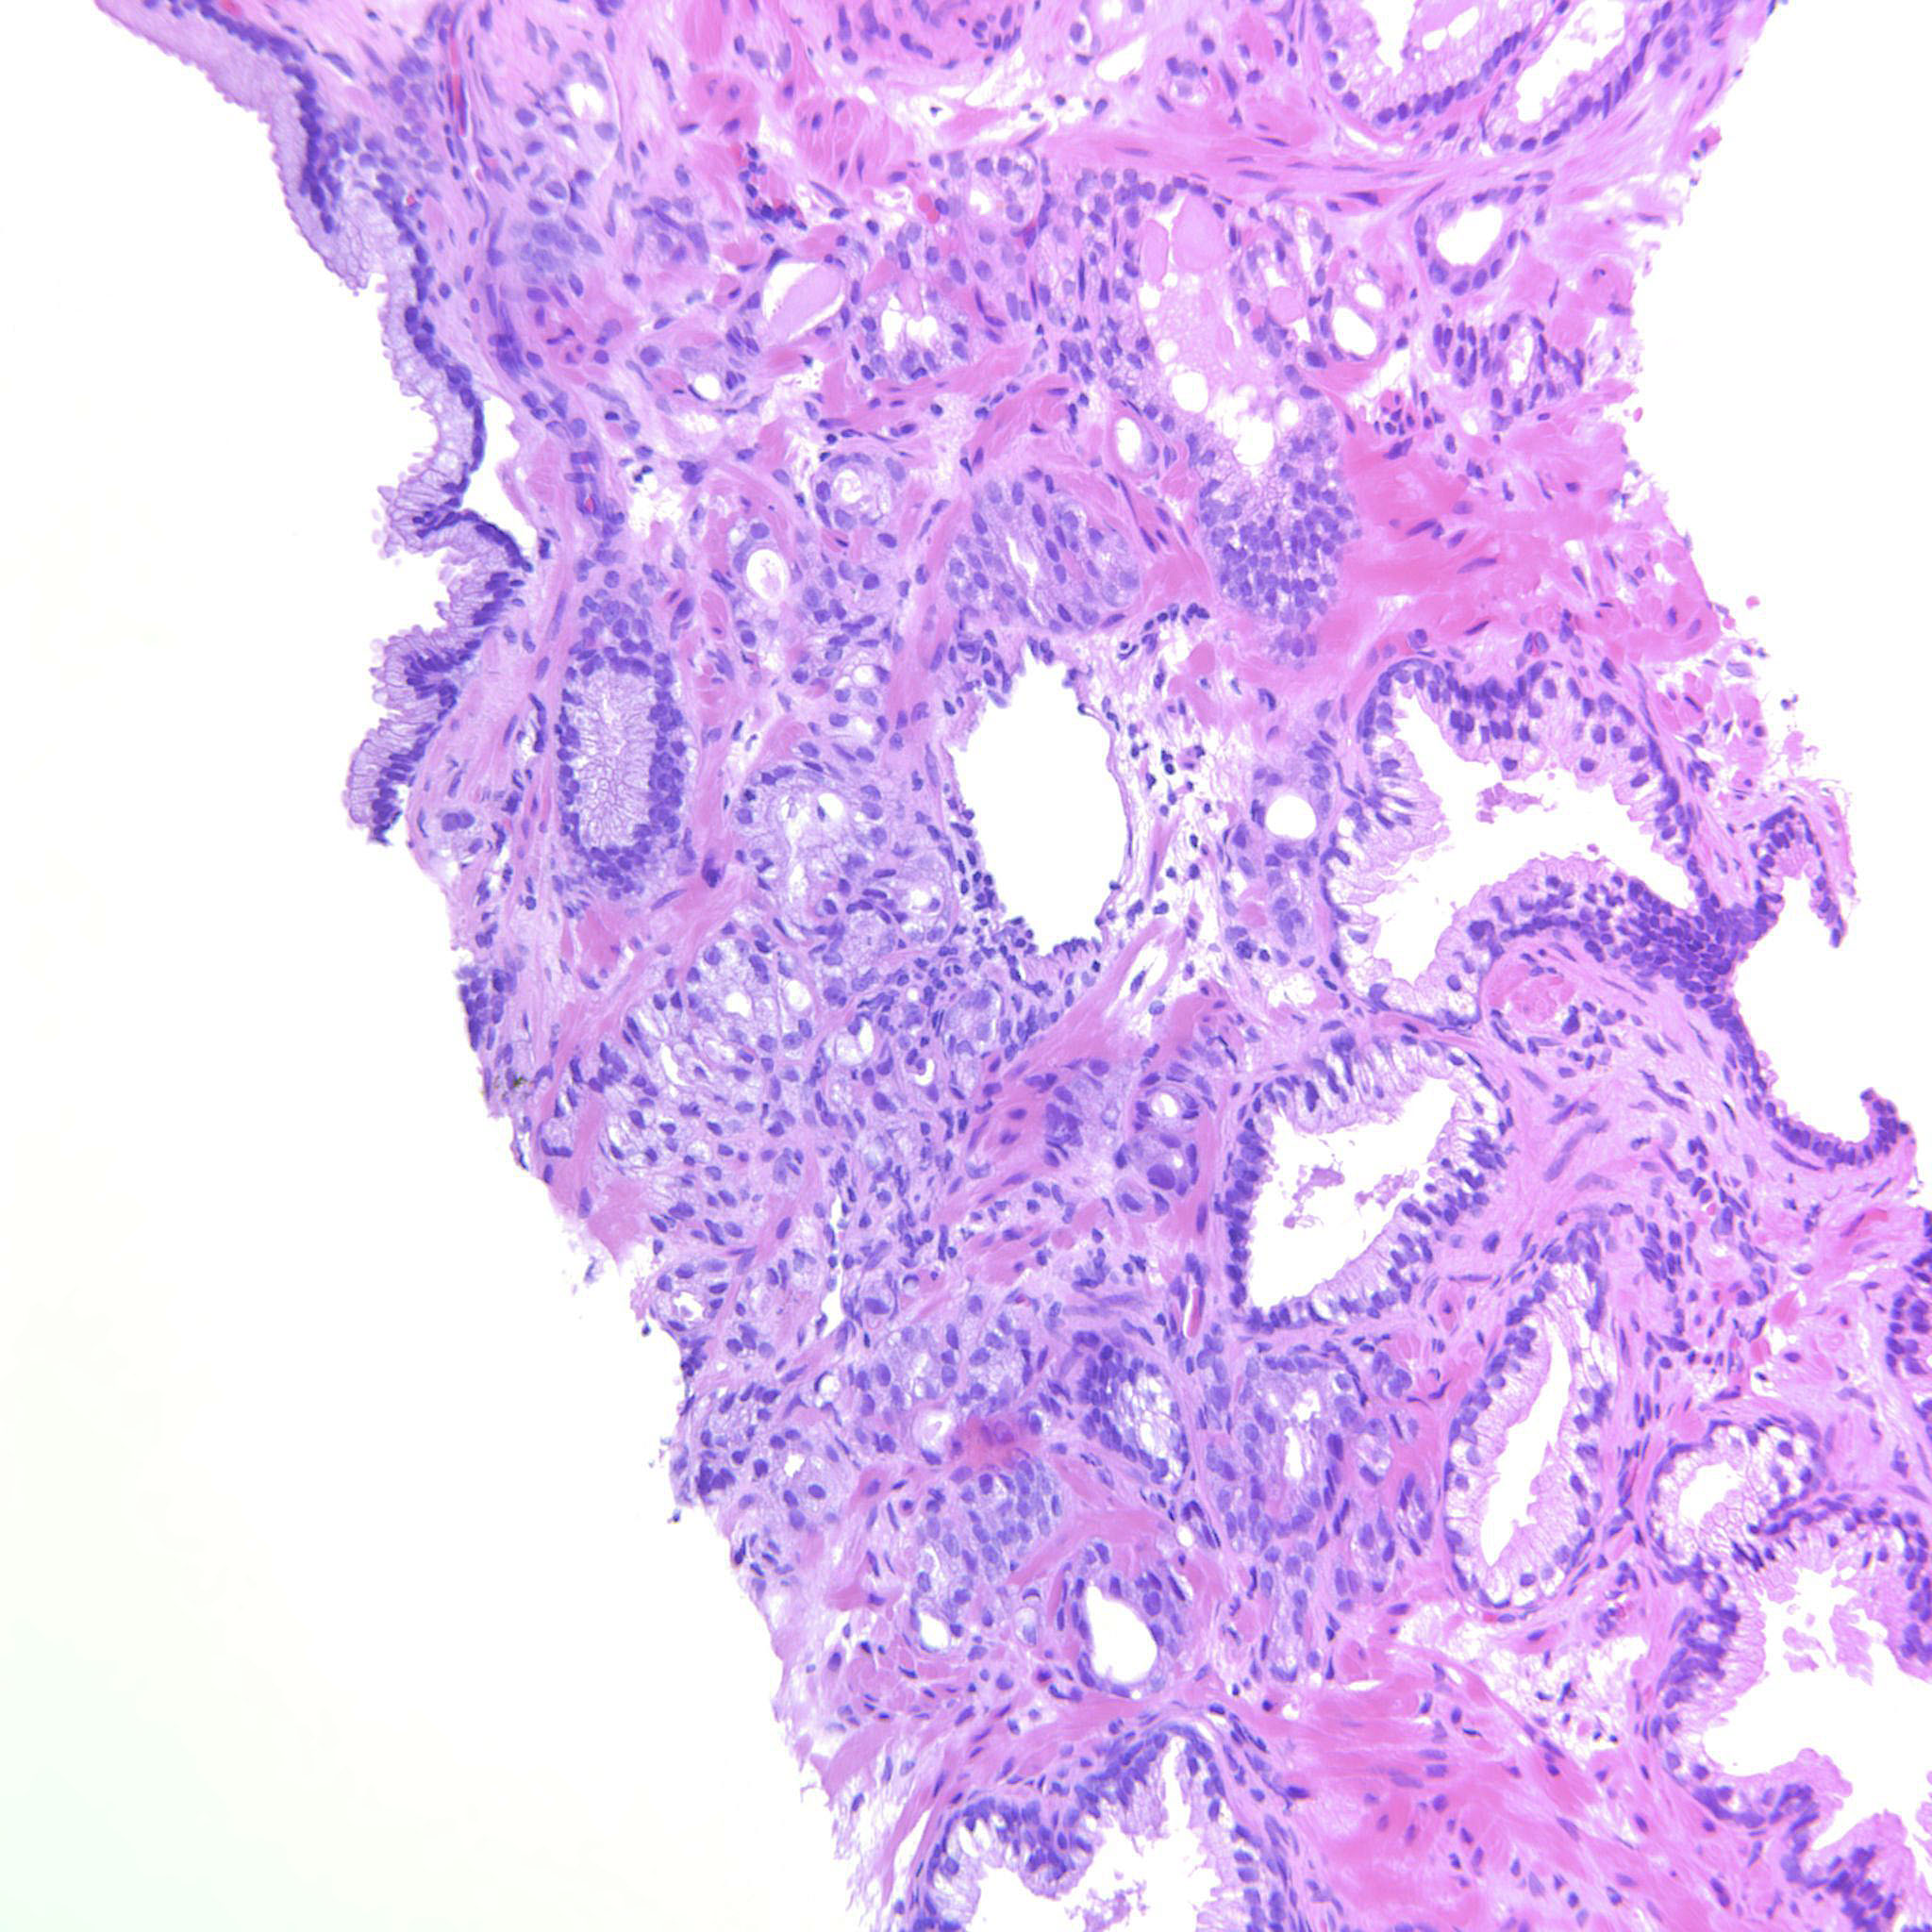

Prostate cancer grading

Case ID: 565